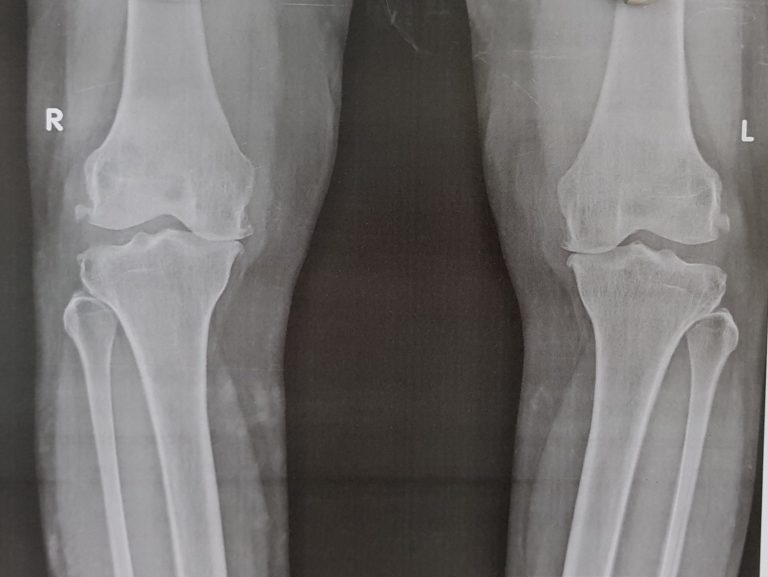

Bilateral Knee Replacement Facts Dental Surgery Before Knee Replacement There is little evidence to support universal dental clearance before tja, even for higher risk patients. Patients should be in optimal oral health prior to having total joint replacement and should maintain good oral hygiene and oral health following. If knee replacement, hip replacement, or heart valve replacement surgery is in your future, you need dental clearance well in advance.. Dental Surgery Before Knee Replacement.